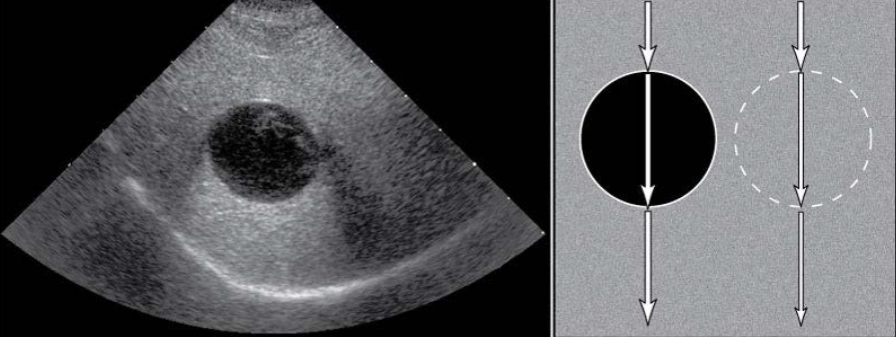

Acoustic Enhancement

increased echogenicty of tissue deep to an area or structure

often seen deep to fluid filled structures